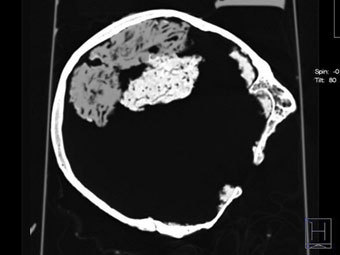

Сканирование найденного в Йорке черепа. Фото ©AFP

В Университете Йорка на севере Англии в ходе земляных работ был обнаружен череп, внутри которого сохранился мозг, передает в пятницу агентство Associated Press.

По мнению ученых, черепу более 2000 лет, что делает его древнейшей находкой такого рода на территории Великобритании и одной из древнейших в мире. Мозг достаточно хорошо сохранился, хотя пока нельзя сказать, обнаружен ли весь орган или только его часть.